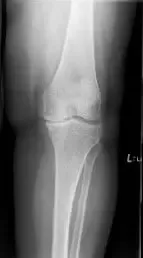

His physical examination revealed tender joint movements with crepitus. There was tenderness on the medial joint line and medial patellar facet. Imaging studies revealed bicompartmental Osteoarthritis of the knee with joint space obliteration of the medial compartment and the patellofemoral compartment.

Pre operative X-Ray of the left knee showing AP and lateral views